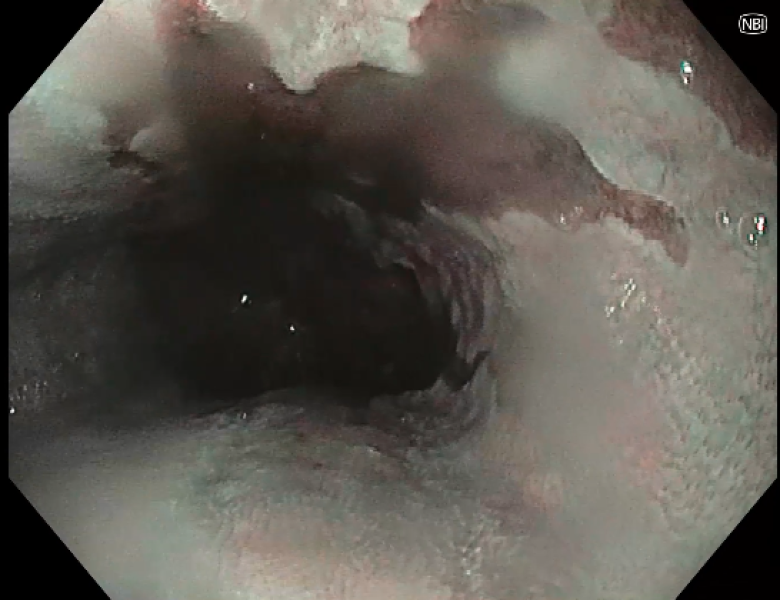

Swiss Cheese Esophagus

Fotografia